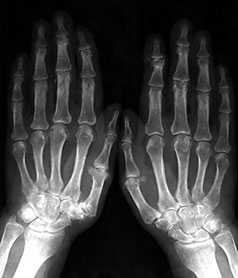

Выраженные изменения (соответствуют 3-4 стадиям артроза по Kellgren):

Умеренно выраженные или крупные остеофиты, деформация краев суставных поверхностей, значительное сужение суставных щелей, остеосклероз (узелки Гебердена в дистальных межфаланговых суставах и узелки Бушара в проксимальных), кисты со склеротическим ободком, краевые дефекты суставных поверхностей, при этом костные выступы с одной стороны могут вклиниваться в другую. Обычно краевые дефекты окружены зоной остеосклероза (рис. 3).

Рис. 3. Обзорная Rо-графия кистей.

Множественные артрозы дистальных и проксимальных межфаланговых суставов. Множественные узелки Гебердена и Бушара. Выраженный артроз 1-го левого запястнопястного сустава